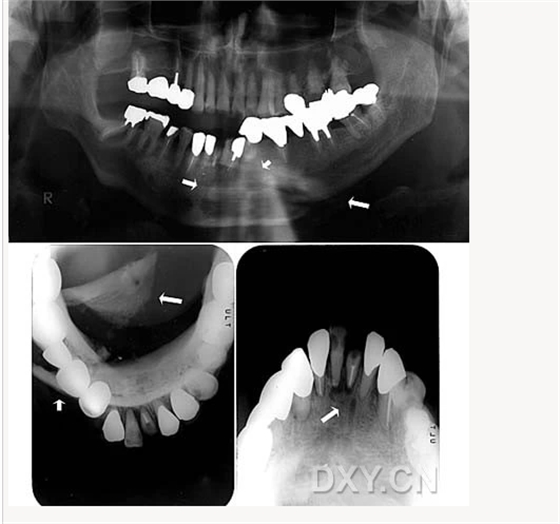

涎石病